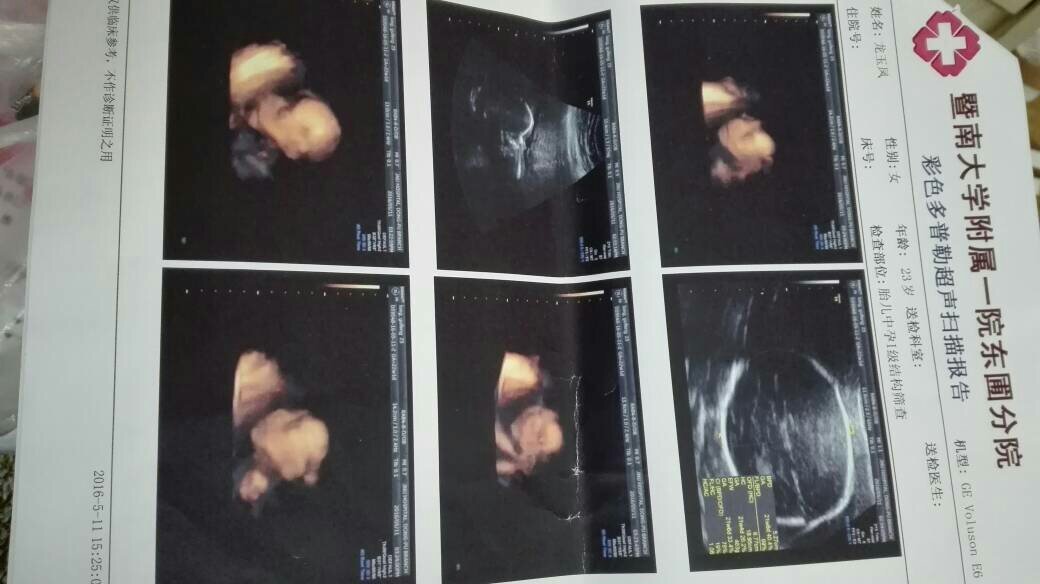

去照了4维,小宝宝脑袋下面蓝色的是什么 点击展开 匿名用户 2016-05-13 14:10 满意回答 您好!结果没有报出胎儿有什么异常,就勒搂没关系,以上只是照裕导片,蓝色可能是血北搁训管! fang 2016-05-13 15:01 宝宝知道提示您:回答为网友贡献,仅供参考。 相关问题 有些小宝宝的眼珠是淡蓝色的是怎么回事? 养一个小宝宝 有粉色或蓝色的 这个游戏叫什么 仓鼠,你们说买哪个,大一点的(蓝色)只是增加了二十块钱…主要是想以后仓鼠生小宝宝哪个好